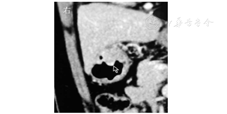

患者女,59岁,因上腹部烧灼感3年余、加重1年于2016年3月1日入院。2013年3月6日的胃镜检查显示慢性浅表性胃炎。2015年7月23日的胃镜检查显示胃体下段前壁有隆起性病变,大小约2.0 cm×2.0 cm,中央溃疡大小约0.5 cm×0.5 cm;病理检查显示慢性重度浅表活动性炎。2016年1月28日的胃镜检查显示胃体、胃窦交界处有隆起性病变,大小约2.5 cm×3.0 cm,中央浅凹溃疡灶大小约0.5 cm×0.6 cm;病理检查显示慢性中度浅表活动性炎。2016年2月18日的CT检查显示胃壁增厚,胃体小弯侧占位(间质瘤不除外),未见肿大淋巴结,见图1。入院后体格检查:体温为36.5 ℃,脉搏为78次/min,血压为130/85 mmHg (1 mmHg=0.133 kPa),一般情况可,未发现明显异常体征。胃镜检查显示胃体下部前壁有2.5 cm×3.0 cm大小的隆起性病变,中央溃疡大小约0.5 cm×0.6 cm,见图2A。超声内镜检查显示病灶处为低回声团块,内部回声欠均匀,起源于固有肌层,向腔外突出,怀疑胃间质瘤,见图2B。患者CEA、CA19-9、CA125等实验室指标均未见异常。排除相关禁忌证后,在全身麻醉下行内镜黏膜下剥离术(endoscopic submucosal dissection,ESD)。病灶周围在黏膜下注射靛胭脂,抬举征阴性;予Dual刀标记并环周切开,见图3A和图3B;继续予Dual刀及末端绝缘刀剥离黏膜及黏膜下病灶,见图3C和图3D;创面予热活检钳电凝止血,术后创面无活动性出血,病灶剥离完整,见图3E和图3F。术后病理显示,黏膜下见一大小约2.2 cm×1.5 cm×1.0 cm的病灶,边界清晰,见图4A;增生的淋巴组织间见散在成巢排列的异型细胞,伴反应性淋巴滤泡形成,见图4B。免疫组织化学检查显示,细胞角蛋白(cytokeratin,CK)5/CK6均阳性,见图5A;P40蛋白质阳性,见图5B;P63阳性;Ki-67为30%;CK7、CK20、CD20、CD3、CD5、CD56、突触素、嗜铬素A、CD34、CD31、CD23和CD21均阴性。原位杂交证实EB病毒感染存在,见图5C。病理诊断为胃淋巴上皮瘤样癌(lymphoepithelioma-like carcinoma,LELC)。与患者充分沟通,行鼻咽镜和全身正电子发射计算机断层显像(positron emission computed tomography, PET)/CT检查排除转移性癌后,接受腔镜下远端胃大部切除术并淋巴结清扫,术后病理示原肿块已切除,符合术后改变,周围未见癌残留,两切端未见癌累及,淋巴结未见癌转移(0/17)。至截稿,患者仍在随访中。